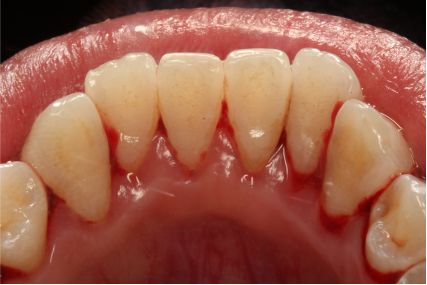

采用PT5牙周治疗仪进行全口超声龈上洁治术、超声龈下刮治术。术后5周复查可见牙龈炎症明显减轻,仍有轻度炎症,复查发现患者口腔卫生维护欠佳,再次进行口腔卫生宣教。

超声洁刮治术后5周